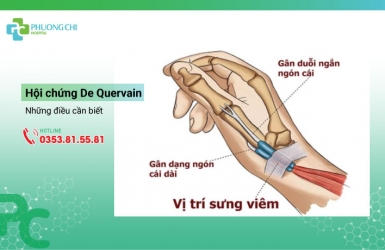

Hội chứng De Quervain và những điều cần biết

Bạn có bao giờ thức dậy vào buổi sáng với đau nhức ở bên ngón cái của cổ tay hoặc gặp khó khăn trong việc duỗi hoặc dạng ngón tay cái hay không? Điều đó có thể là do bạn đang bị hội chứng De Quervain hay còn gọi là viêm bao gân dạng dài và duỗi ngắn ngón cái, một tình trạng phổ biến gây suy giảm chức năng dẫn đến việc thực hiện các công việc hằng ngày trở nên bất tiện và khó khăn, ảnh hưởng tới chất lượng sống của người bệnh.